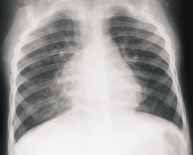

Este tipo de infecciones comprometen principalmente la mucosa respiratoria y las vías aéreas, ocasionando inflamación y necrosis de las células ciliadas, células globosas y glándulas de la mucosa bronquial que llevan a edema de la pared bronquial y bronquiolar, que se manifiestan radiológicamente como opacidades peribronquiales, usualmente simétricas y radiadas de los hilios a la periferia (Figura 1).

FIGURA 1. Proyección AP de tórax con neumonía viral en la cual existen infiltrados intersticiales parahiliares

radiados desde el hilio a la periferia en ambos parénquimas pulmonares.